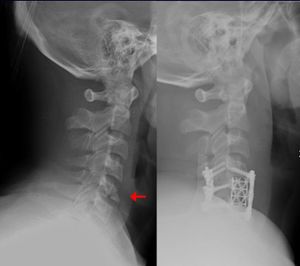

جراحة العظام هو فرع من فروع الجراحة الجراحية في الطب ويتخصص في مشاكل الجهاز العظمي والعضلي. ويستخدم جراح العظام الوسائل الجراحية وغير الجراحية لعلاج الحوادث المتعلقة بالجهاز العظمي والعضلي وأصابات الملاعب والعيوب الخلقية والآفات التنكسية الناتجة من كبر السن.

طب العظام يعنى بشكل عام بتصحيح الكسور جراحيا وتجبيرها إضافة إلى عمليات إصلاح وتبديل المفاصل التالفة. بالإضافة إلى أنواع أخرى من العمليات الجراحية التي تعالج أمراض العظام والجهاز الحركي.

جراحة العظام فرع من فروع الطب يعالج اعتلالات العظام والعضلات والأنسجة المتصلة بها. ويُدعى الأطباء الذين يُمارسون جراحة العظام جراحو العظام. وهم يُعالجون مُشكلات طبية كثيرة في هذا المجال منها الكسور، وإصابات الأوتار والأربطة، وتشوهات الأطراف والعمود الفقري. وقد توجد بعض الاعتلالات العظمية منذ الولادة، بينما تظهر اعتلالات أخرى أثناء الطفولة بسبب مشكلات تتعلق بالنمو، أو في فترة متأخرة من العمر نتيجة للشيخوخة. كما تحدث اعتلالات أخرى نتيجة إصابة ما أو مرض. ويُشكل المصابون في حوادث السيارات، أو الأنشطة الرياضية أو أثناء التنزه والاستجمام عددًا كبيرًا من المرضى الذين يعالجهم اختصاصيو العظام. ويصف الأطباء لمعالجة الاعتلالات العظمية الأدوية، والجراحة، والعلاج الطبيعي. وقد يقوم الاختصاصي، على سبيل المثال، بإجراء جراحة لتقويم كسر أو تشوه. وبعد الجراحة قد يستخدم الاختصاصي قالبًا أو مقبضًا، ويصف العلاج الطبيعي كي يساعد على الشفاء. مثل هذه المعالجة قد تشمل استخدام جهاز يطلق نبضات كهربائية تُساعد العظم على الالتئام. كما قد يقوم الاختصاصي بإجراء جراحة لاستبدال مفصل من البلاستيك أو المعدن أو من مواد أخرى بمفصل ملتهب، أو مصاب. والمفصل الذي يستبدل عادة أكثر من غيره، هو مفصل الورك.

- جراحة العمود الفقري